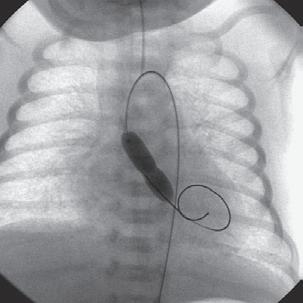

E-FIGURE 1-1 Devices that are increasingly available to provide assistance during high-risk percutaneous coronary intervention (PCI) include percutaneous extracorporeal circulatory support devices such as (A, B) the TandemHeart and (C) the Impella device. (A) The TandemHeart removes oxygenated blood from the left atrium and returns this blood into the peripheral arterial circulation; with the (B) aid of a centrifugal pump. C, The Impella left ventricular assist device is a miniaturized rotary blood pump that is placed retrograde across the aortic valve, and it aspirates (inlet area) up to 2.5 L/min of blood from the left ventricular cavity and subsequently expels this blood (outlet area) into the ascending aorta. (From Valgimigli M, Steendijk P, Serruys PW, et al: Use of Impella Recover LP 2.5 left ventricular assist device during high-risk percutaneous coronary interventions; clinical, haemodynamic and biochemical findings. EuroIntervention 2[1]:91-100, 2006; and Vranckx P, Meliga E, De Jaegere PP, et al: The TandemHeart, percutaneous transseptal left ventricular assist device: a safeguard in high-risk percutaneous coronary interventions. The six-year Rotterdam experience. EuroIntervention 4:331, 2008.)